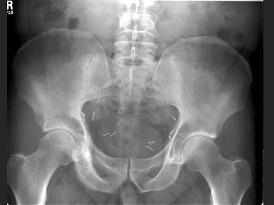

问题 男,56岁,右髋部疼痛,5年前被确诊为前列腺癌,结合图像,最可能的诊断是?(?)

选项 A.骨纤维异常增殖症 B.转移性骨肿瘤 C.畸形性骨炎 D.内生软骨瘤 E.非骨化性纤维瘤

答案 C